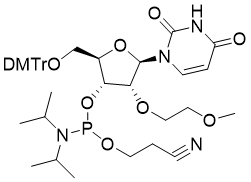

馬鞍山致研生物醫(yī)藥科技有限公司成立于馬鞍山市鄭浦港新區(qū)現(xiàn)代產(chǎn)業(yè)園。公司專(zhuān)注于生物小分子、醫(yī)藥中間體相關(guān)產(chǎn)品的研發(fā)和生產(chǎn),產(chǎn)品主要包括DNA亞磷酰胺單體、RNA亞磷酰胺單體、特殊單體以及按照客戶(hù)要求定制的RNA和DNA,并且公司提供定制合成等方面的研究服...

馬鞍山致研生物醫(yī)藥科技有限公司成立于馬鞍山市鄭浦港新區(qū)現(xiàn)代產(chǎn)業(yè)園。公司專(zhuān)注于生物小分子、醫(yī)藥中間體相關(guān)產(chǎn)品的研發(fā)和生產(chǎn),產(chǎn)品主要包括DNA亞磷酰胺單體、RNA亞磷酰胺單體、特殊單體以及按照客戶(hù)要求定制的RNA和DNA,并且公司提供定制合成等方面的研究服...